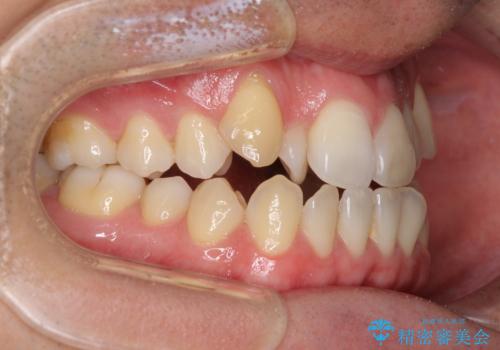

左右の八重歯が気になる ワイヤー装置での咬み合わせ改善

- 八重歯と前歯のデコボコを気にして来院された患者様です。

舌の突出癖がなかなか改善されず、上下前歯部の接触が得られるまでに予定の倍ほどの期間がかかりました。